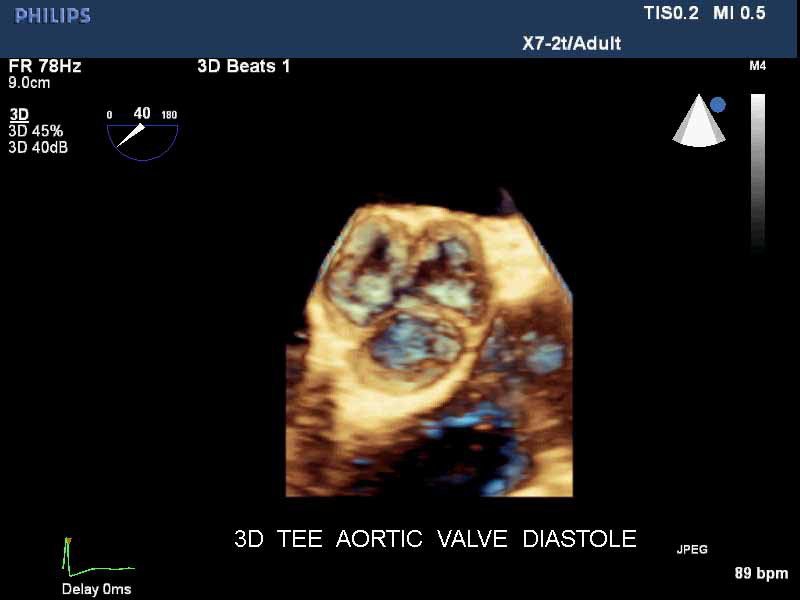

• Live 3D TEE: Эта функция позволяет проводить чреспищеводную эхокардиографию в режиме реального времени, что позволяет оценить механические сокращения сердца с точностью, необходимой для оценки результатов хирургического вмешательства.

• 3D эхо-кг в реальном времени (Live3DEcho): Эта технология позволяет получать объемные 3D изображения сердца в режиме реального времени.